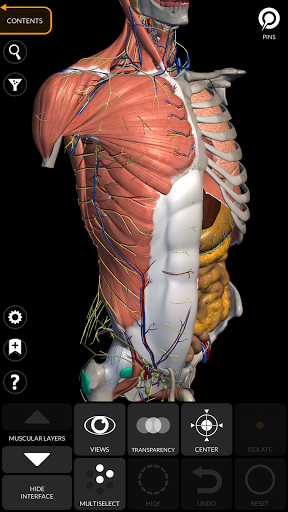

"Anatomy 3D Atlas" cho phép bạn nghiên cứu giải phẫu người theo cách dễ dàng và tương tác.

Thông qua giao diện đơn giản và trực quan, bạn có thể quan sát mọi cấu trúc giải phẫu từ mọi góc độ.

Các mô hình giải phẫu 3D đặc biệt chi tiết và có kết cấu lên đến độ phân giải 4k.

Việc phân chia theo vùng và chế độ xem được xác định trước giúp quan sát và nghiên cứu các bộ phận hoặc nhóm hệ thống riêng lẻ và mối quan hệ giữa các cơ quan khác nhau.

MÔ HÌNH GIẢI PHẪU 3D

• Hệ thống cơ xương

TÍNH NĂNG •

Giao diện đơn giản và trực quan

• Xoay và phóng to từng mô hình trong không gian 3D

• Tùy chọn ẩn hoặc cô lập một hoặc nhiều mô hình đã chọn

• Bộ lọc để ẩn hoặc hiển thị từng hệ thống

• Hình dung các cơ qua các lớp từ lớp nông đến lớp sâu nhất